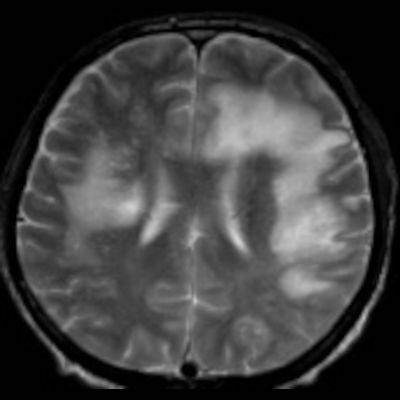

- Bilateral asimetrik subkortikal ve derin beyaz cevherde T1 ağırlıklı görüntülerde belirgin hipointens (oklar), T2A görüntülerde hiperintens (oklar), gri cevhere bakan kesimi düzgün (oklar), DAG’de hiperintens (ok) lezyonlar izlendi. Lezyonlarda T2/FLAIR uyumsuzluğu vardı (ok). Serebellar beyaz cevherde dentat nukleusu koruyan hilal işareti görüldü (ok başı). SWI sekansta sol motor kortekste hipointens kronik glioinflamatuar reaksiyon ile uyumlu sinyal değişikliği izlendi (ok başı).

- Çoğunlukla subkortikal beyaz cevherde ve U fiberlerde, asimetrik, genelde kitle etkisi yapmayan ve kontrastlanmayan demiyelinizan lezyonlar görülür. Korteks ve derin gri cevher tutulumu daha nadirdir.

- PML lezyonları, T1A görüntülerde belirgin hipointenstir. Gri cevhere bakan yüzleri keskin olup T2/FLAIR uyumsuzluğu önemli özelliğidir.